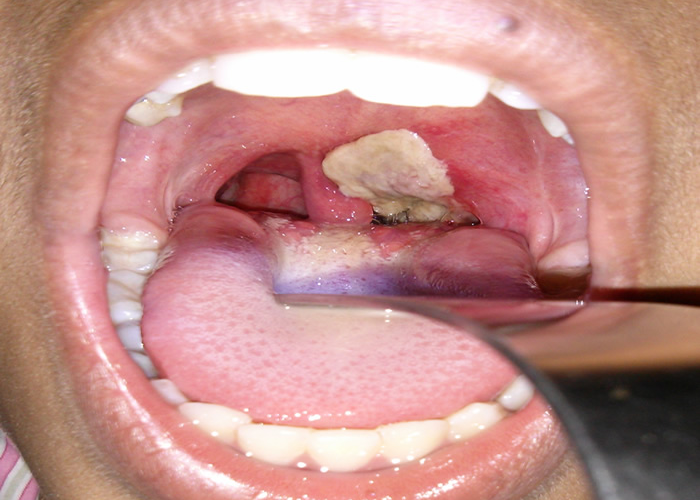

The Nigeria Centre for Disease Control and Prevention has reported approximately 12,085 suspected cases of diphtheria ...